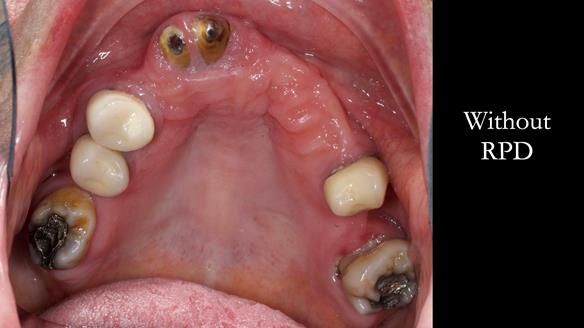

Aesthetically and functionally poor RPDs were replaced for Eileen, a 74 year old woman.

Referred to me by her general dental practitioner specifically for replacement RPDs.

- Missing teeth in the upper and lower jaws

- Upper and lower metal based RPDs, poorly fitting, worn occlusal surface, reverse curve aesthetics, lacking support

- Poor dental appearance with reverse incisal curve

- The upper right central and lateral incisors with post crowns. Healthy and functionally secure but with poor appearance, contributing to the reverse curve.

- Moderate to heavily restored dentition with deep overbite (Class 2 div II)

- Yellowish lower front teeth with small amount of wear.

- The lower right canine (LR3) is worn with MOD cavity.